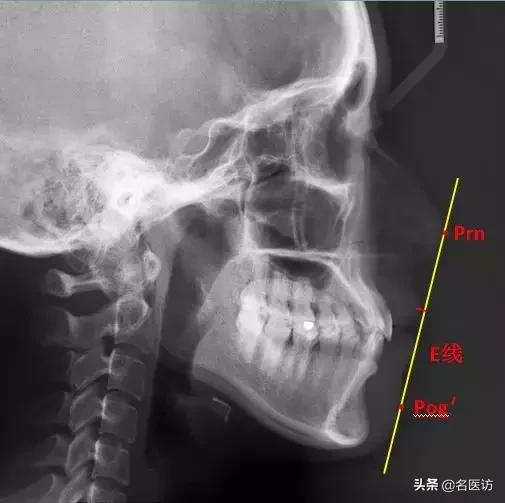

4、评估上下唇凸度:E线

Prn:鼻部最凸点

Pog’:颏部最前点

E线也叫审美平面,是鼻子凸点和颏前点的切线,用来评估上下唇的凸度。据统计,中国成年人上下唇超出E线的占76%,而美丽的成年女性,双唇应该都在E线内。(手动微笑再见!)